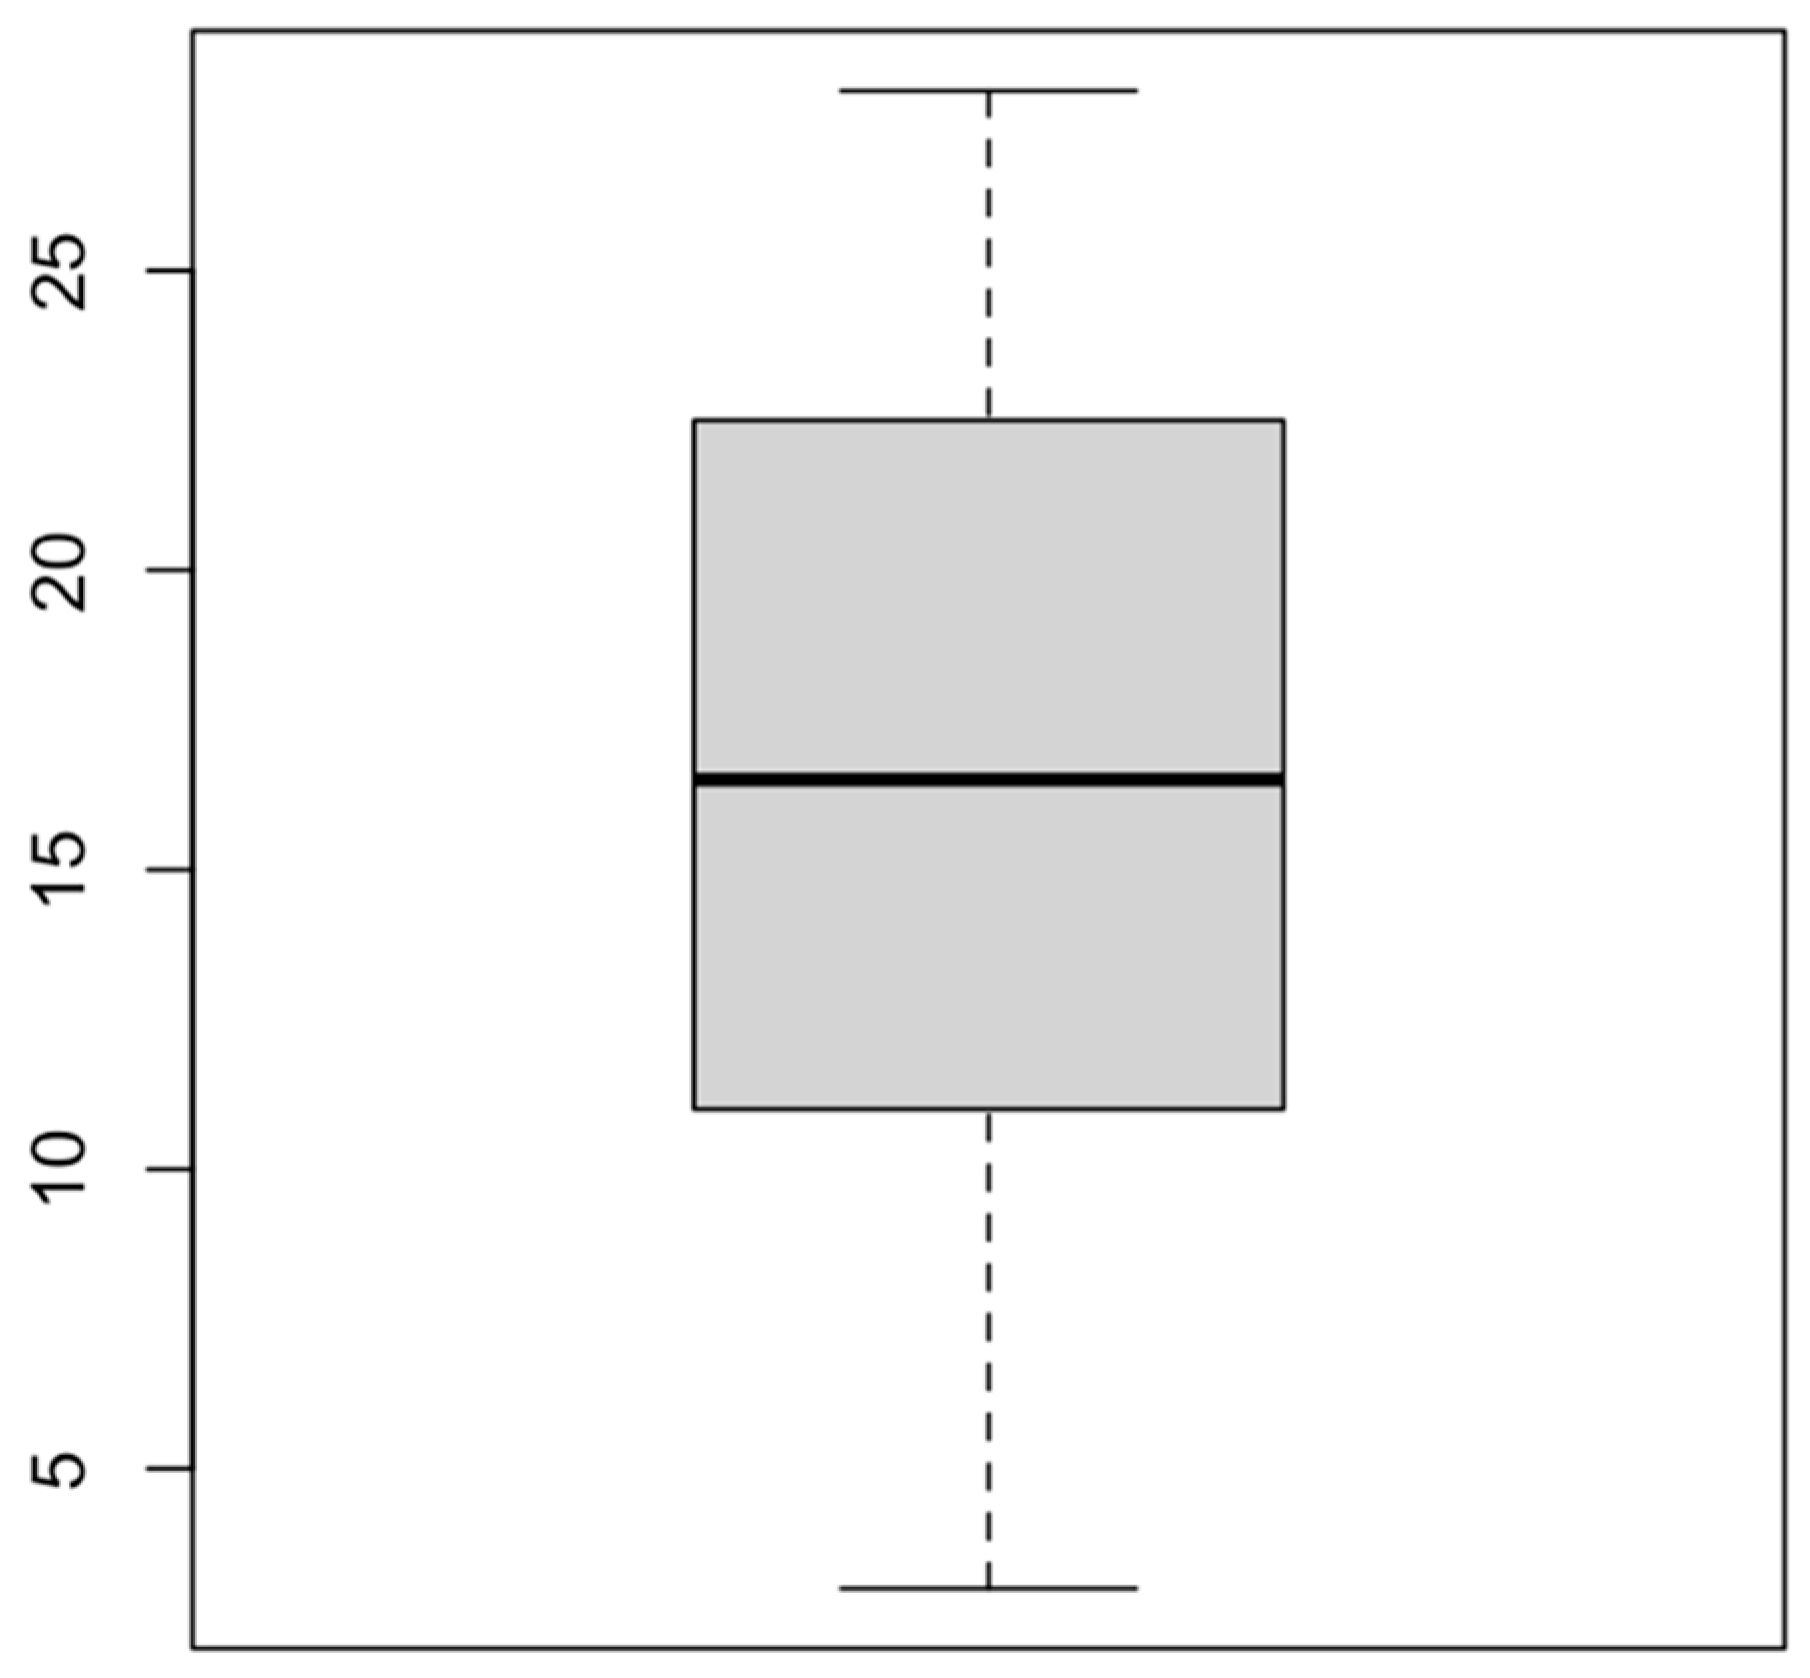

| Length of hospital stay (pediatric unit) | |

| 80 (74.1%) |

| 28 (25.9%) |